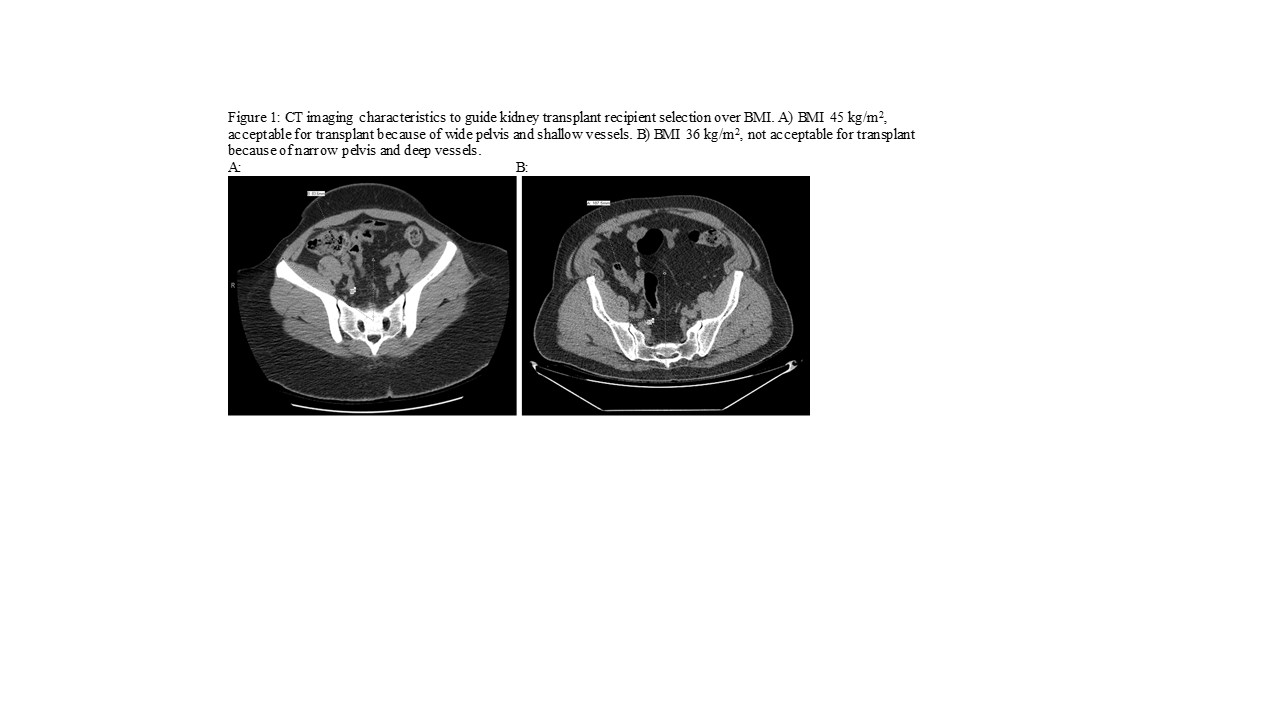

Introduction: Kidney transplantation confers a survival benefit compared with dialysis in most studies of obese patients. Yet, many transplant centers decline patients with a body mass index (BMI) ≥40 kg/m2. Our practice relies on computed tomography imaging to evaluate iliac depth and pelvic angle to assess candidacy (see Figure 1). Our aim was to evaluate post-transplant outcomes including survival in patients according to recipient BMI.